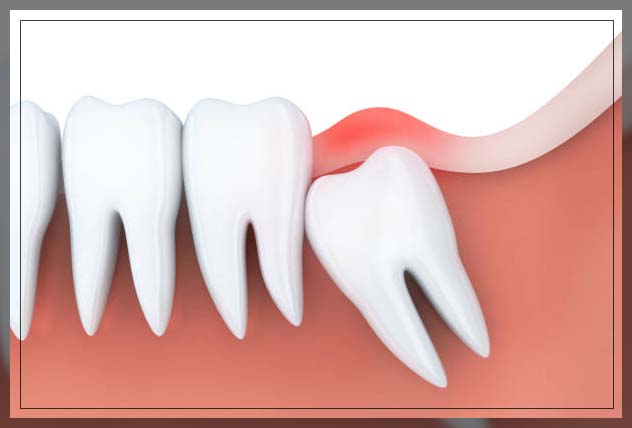

4. Growing Pain

When your wisdom teeth start to hurt, they could be growing in. You will start to have pain at the back of the mouth, especially behind the molars. When the teeth break through your gums, it can cause severe pain, soreness, and slight swelling. Your third molar will emerge after all the adult teeth.

Sometimes they emerge at an awkward angle, or there may not be enough room for them. In such a scenario, the pain will gradually increase with time as your wisdom teeth continue to grow misaligned or sideways. Slowly, they will press on the nerves, bone, and crowded surrounding teeth.